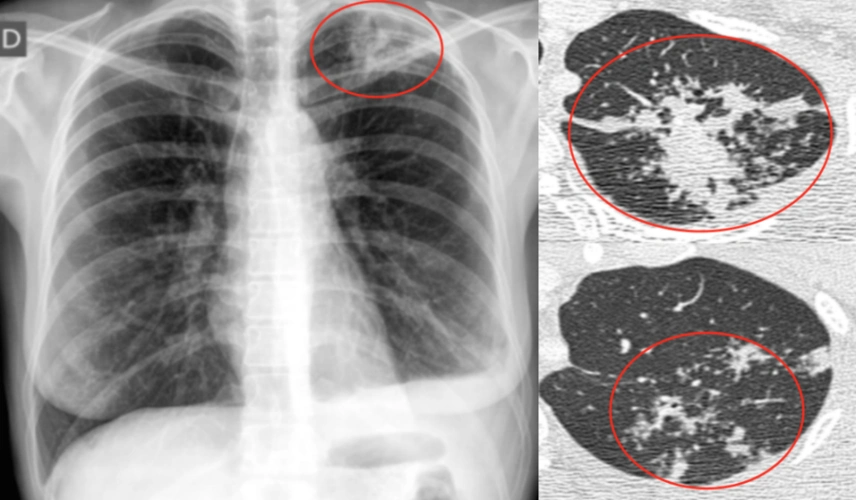

陈起航教授:肺结核的影像学评价——遏制,终止,终结肺结核(2)_腾讯